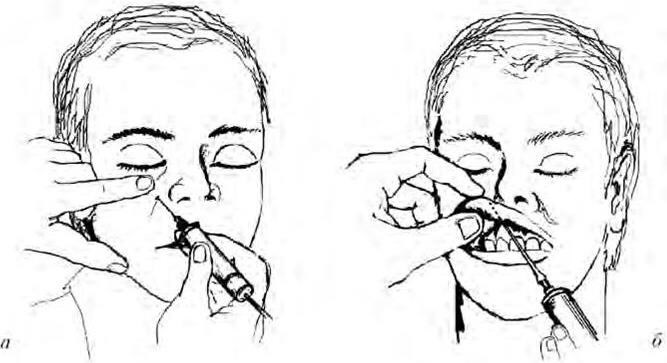

Внутриротовой доступ: обезболивание может быть проведено аподактильно или после предварительного ощупывания костных анатомических ориентиров. Анестезию после предварительного ощупывания начинают с пальпаторного определения позадимолярной ямки и височного гребешка, который и является ориентиром для вкола иглы. При широко открытом рте инъектор располагают на уровне премоляров противоположной стороны и вкалывают иглу кнутри от височного гребешка на 0,7 – 1,0 см выше поверхности смыкания близстоящего зуба, продвигая ее кнаружи и кзади до соприкосновения с костью. Выводят часть анестезирующего раствора, чем достигают блокирования язычного нерва. Продвинув иглу вглубь еще на 2 см и достигнув костного желобка, вводят оставшуюся часть раствора анестетика, блокируя нижний луночковый нерв (рис. 1.6, а).

Рис. 1.6. Обезболивание нижнелуночкового нерва у нижнечелюстного отверстия:

а – внутриротовой доступ; б – внеротовой доступ